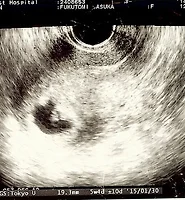

아스카와 노하라는 오래간만에 물놀이를 하러 가미가모 신사에 놀러갔습니다.

가미가모 신사는 예전에 장인어른 장모님도 아스카를 데리고 물놀이를 하러 자주 갔던 곳 입니다.

저는 이날 같이 가지는 못했지만, 물놀이를 하러 많이 놀러온듯.